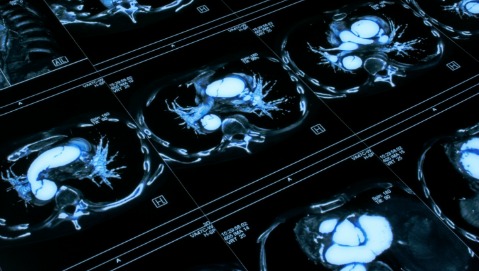

Dei tumori del polmone rilevati con una Tc spirale, 82 su cento sono effettivamente malattie pericolose, mentre 18 su cento probabilmente non sarebbero mai diventati significativi dal punto di vista clinico.

E’ la stima più recente del tasso di sovradiagnosi nello screening per il carcinoma polmonare in persone ad alto rischio. Pubblicata sulla rivista JAMA Internal Medicine, è il frutto di uno studio sui dati del National Lung Screening Trial, sostenuto dai National Institutes of Health, che ha confrontato la Tc spirale a basse dosi con la radiografia del torace in oltre 53.000 persone.

COSTI E BENEFICI - La sovradiagnosi, cioè l’individuazione di tumori indolenti o a crescita lenta, è un rischio insito in ogni screening, che è chiamato appunto a rilevare malattie in uno stadio precoce, quando ancora non hanno dato sintomi, così da aumentare le possibilità di cura e guarigione, e permettere l’uso delle terapie meno invasive possibili. E’ evidente che, nel caso della Tc spirale, l’obiettivo sia ridurre al minimo i costi e l’esposizione del paziente a radiazioni ionizzanti, sia pure in dosi molto basse, e a stress fisico e psicologico. La questione è tuttora dibattuta fra gli addetti ai lavori, ma l’esame ha mostrato di ridurre la mortalità per cancro del polmone nei forti fumatori, tanto che alcuni mesi fa l’American Cancer Society, la maggior charity al mondo in campo oncologico, ha incluso nelle sue linee guida l’indicazione allo screening per le persone a rischio, purchè adeguatamente informate sui benefici, limiti e rischi della metodica, e purchè i controlli vengano eseguiti in centri di elevata esperienza nella diagnosi precoce del tumore polmonare.